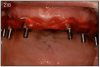

Completely Edentulous

Many fearful dental patients avoid dental treatment, resulting in loss of teeth due to periodontal disease or extensive decay. With the advancements in today's dental implant technology, the dentist can insert implants immediately following extractions and deliver a fixed temporary full-arch prosthesis connected to the implants.31 Many patients are unaware of this option, and it is a preferred options since many of them are fearful of getting a denture. It is the responsibility of the dental team to educate the patients and become familiar with the new implant options.

After 4-6 months of healing, the final fixed bridge can be fabricated. This can be made out of acrylic reinforced by a CAD-CAM milled framework or out of porcelain with a titanium or zirconia framework. Both can achieve a great esthetic result, but porcelain is 3 to 4 times more expensive. Recent studies show that it is beneficial to splint implants together with an immediate, fixed temporary prosthesis because it decreases their risk of implant failure compared to using a removable transitional denture.19

As stated earlier, dentures replace only about 10% of chewing function. This causes digestive problems, due to an inability to chew food properly, also leading to malnutrition, due to an increase in consumption of softer, more processed foods. This inability to chew also results in atrophy of the alveolar arches due to lack of adequate pressure on the bone. When the denture is pressing on the mental foramen, then patients will experience pain and numbness of the lower lip. A good solution for these denture wearers is to place 2 to 4 implants in the mandible to stabilize the denture. The denture is then attached to the implants via snap-on attachments or a bar. (Figures 13A-C) According to the 2002 McGill Consensus Statement on Overdentures, mandibular two-implant overdentures are superior to conventional dentures in all clinical trials, even up to nine years in function.32